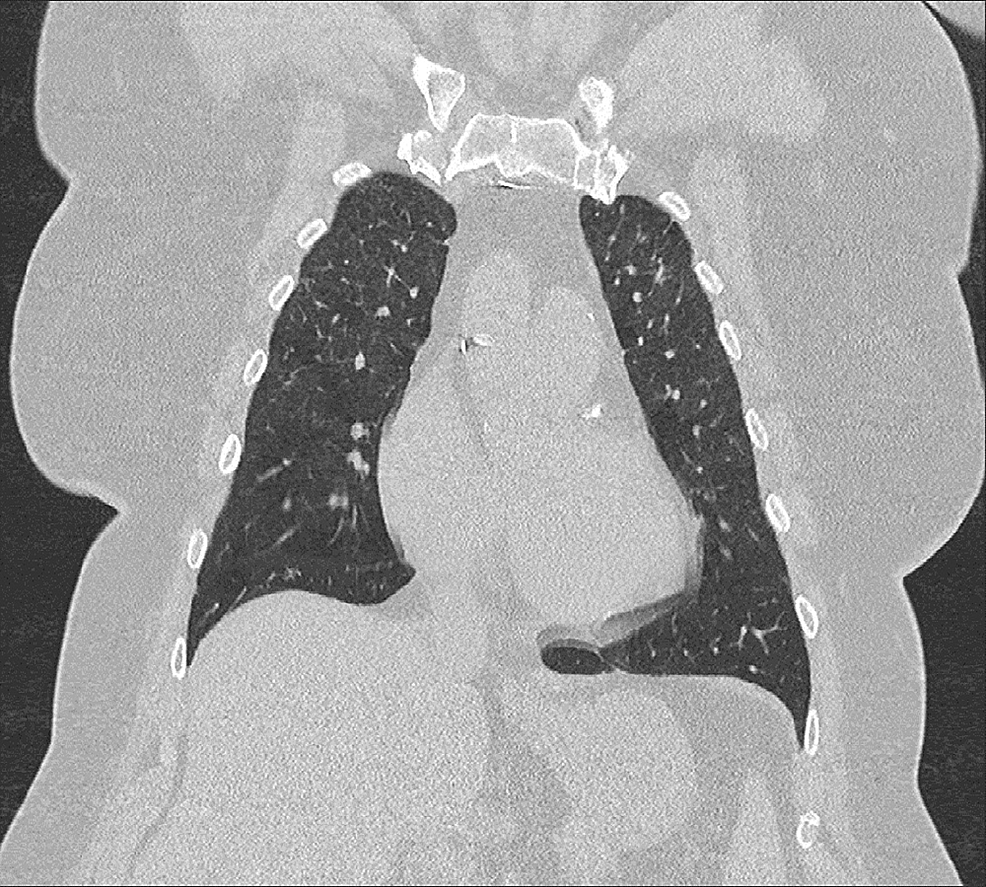

CT Findings of Granulomatous Pneumonitis Secondary to Mycobacterium How Common Is Hot Tub Lung A persistent and dry cough is a common symptom of hot tub lung. Dyspnea and cough were present in all patients,. we identified 21 patients who fulfilled our diagnostic criteria for hot tub lung including: hot tub lung (htl) is a granulomatous lung disease thought to. hot tub lung is a specific form of hypersensitivity pneumonitis caused. How Common Is Hot Tub Lung.